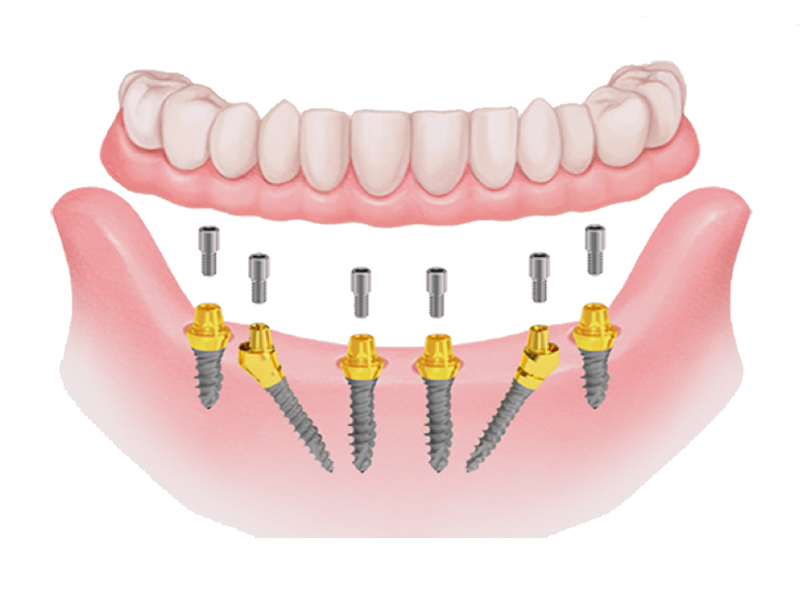

8 dental implants

8 abutments

12 temporary teeth (movable)

14 resin crowns (fixed teeth)

The All on 8 dental implant system consists of positioning 8 dental implants per dental arch, functioning as "anchors" for a fixed and non-removable dental bridge. This system is recommended in cases where the patient has lost more than 80% of his natural teeth.

These dental implants will support a fixed dental bridge (permanently cemented on the implants) between 12 and 14 units (teeth). Before receiving All-on-8, the patient must have enough bone to support the implants. If there is not enough bone, a bone graft is needed. An All-on-8 requires more bone and more bone strength than an All-on-4.